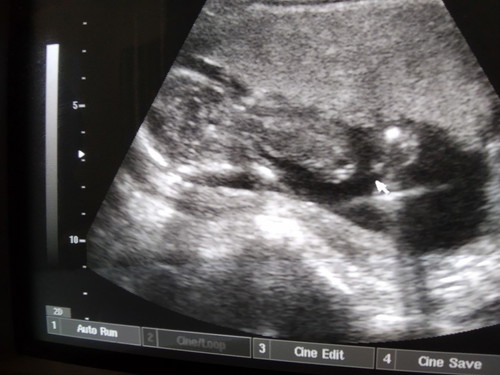

คุณหมอบอกแม่ว่าหนูเป็นผู้ชายครับ 17w คุณแม่ท่านไหนพอจะมองออกบ้างคะ

ตรงลูกศรน่าจะใช่จ้า จุ๊ดจู๋